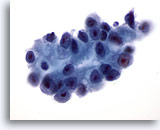

画像 1

肺FNA、単純ヘルペスウイルス肺感染症

多核化、核の相互圧排、スリガラス様クロマチンのほか、好酸性の核内封入体などウイルス性細胞変性に特徴的な様相が認められます。

60倍

画像 1

肺FNA、単純ヘルペスウイルス肺感染症

多核化、核の相互圧排、スリガラス様クロマチンのほか、好酸性の核内封入体などウイルス性細胞変性に特徴的な様相が認められます。

60倍